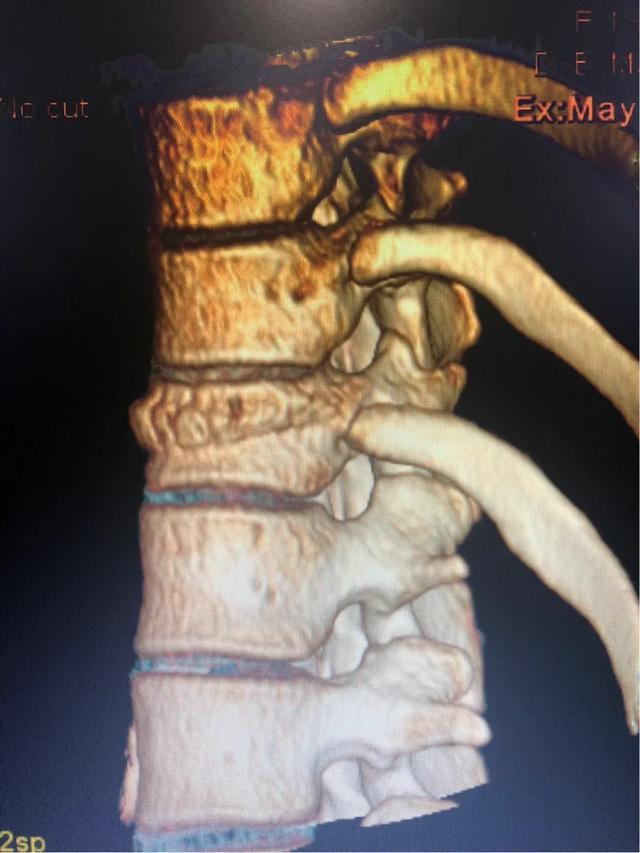

三维CT看的清楚